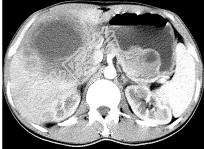

单项选择题女,61岁, 上腹部疼痛一个月,食欲减退, 消瘦,CT所见如图, 最可能的诊断是 ( )

A、肝脓肿

B、肝转移瘤

C、胃癌肝转移

D、肝包虫病

E、原发性肝癌